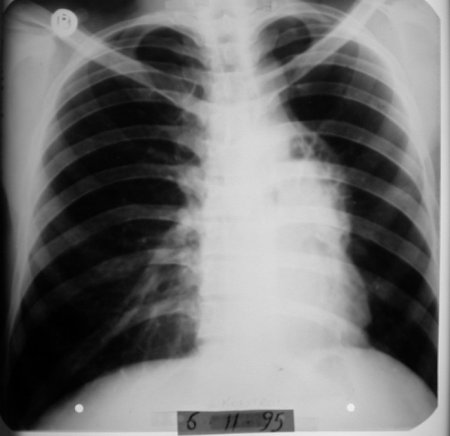

Röntgende kitle küçülmüş durumda görüldü.

Röntgen tümörün tamamen kaybolduğunu gösterdi.